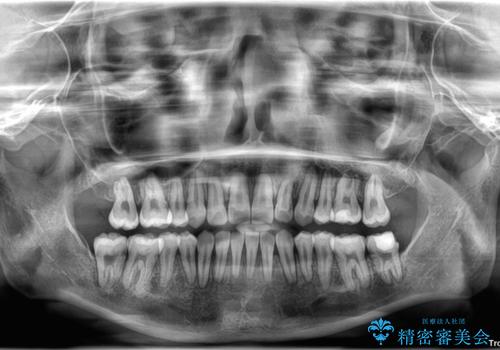

上顎前歯部はデコボコが強く、歯を並べるためのスペースが不足しているため、左右の第一小臼歯を抜歯することとしました。

また、抜歯して確保したスペースが不足してしまうのを防ぐため、補助装置を併用しています。

補助装置を併用したおかげで、出っ歯になることなくスムーズに治療を終えることができました。